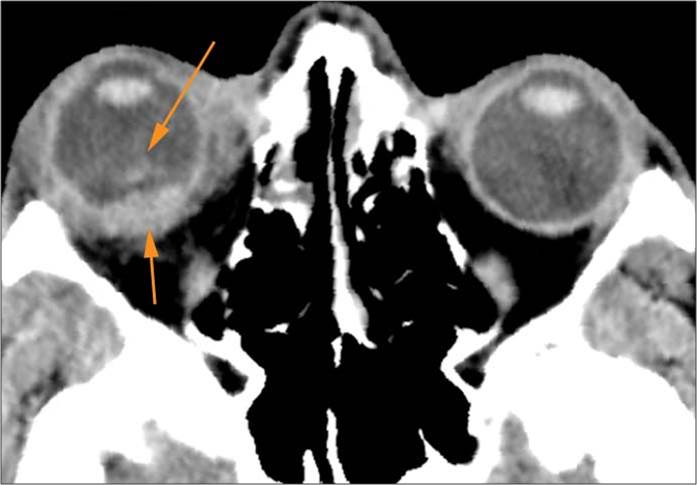

Zygomatico-orbital region and globes

The circumferential extraconal and the intraconal orbital fat including that of the orbital apex are edematous or otherwise abnormal.

There is evidence of tension orbit.